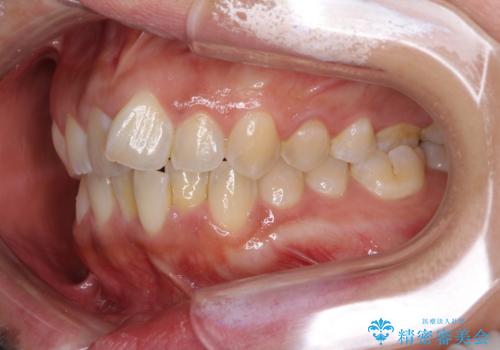

インビザラインによる狭窄歯列の拡大矯正

- 前歯のデコボコを治したいとのことで来院された患者様です。

上下顎ともに歯列全体の後方移動と側方拡大、IPR(歯と歯の間を削る)によってデコボコが解消するように設計し、インビザラインにより治療を行うこととしました。

後方移動に際し、上下の親知らずは4本とも抜歯することとしました。